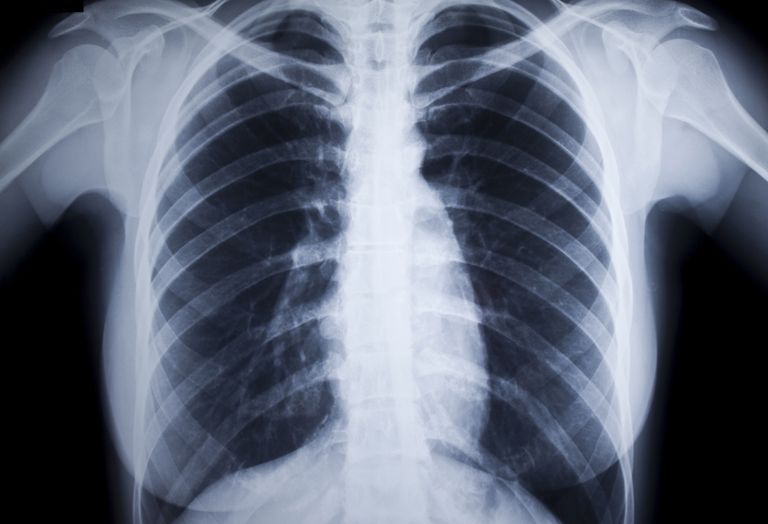

Как понять, что с легкими проблемы?

Во многом заболевания дыхательной системы схожи по симптоматике и начальным проявлениям, при этом все они по-разному воздействуют на органы. Например, астма приводит к повреждению легочных тканей. Заподозрить эту болезнь можно по громким хрипам, кашлю, «синеватым» покровам и чиханию.

Острый бронхит сильнее проявляется по ночам, сопровождается кашлем с резкой болью в груди. При хронической форме кашель становится постоянным. Плеврит отличается от бронхита тем, что боль возникает в груди не только при кашле, но и при малейших движениях торса.

Для пневмонии наиболее характерным симптомом считается устойчивое повышение температуры тела и затрудненное дыхание. При этом кашля может не быть. Больные чувствуют себя обессиленными, их беспокоит присутствие ощущения тревоги, взволнованности, слабость в мышцах и апатия.

Признаки эмфиземы могут не проявляться вплоть до последних стадий заболевания. У пациентов отмечается стремительная потеря массы тела, изменение цвета кожных покровов, происходит бочкообразная деформация грудной клетки. Как правило, больному эмфиземой даже выдох дается с трудом.

Сложнее всего диагностировать на ранних стадиях злокачественную опухоль легких. Признаки онкологии часто принимаются пациентами за симптомы банальной простуды. Многие не берут во внимание затяжной характер своего недомогания, нетипичный для респираторного заболевания, и обращаются за помощью, когда возникают реальные проблемы.